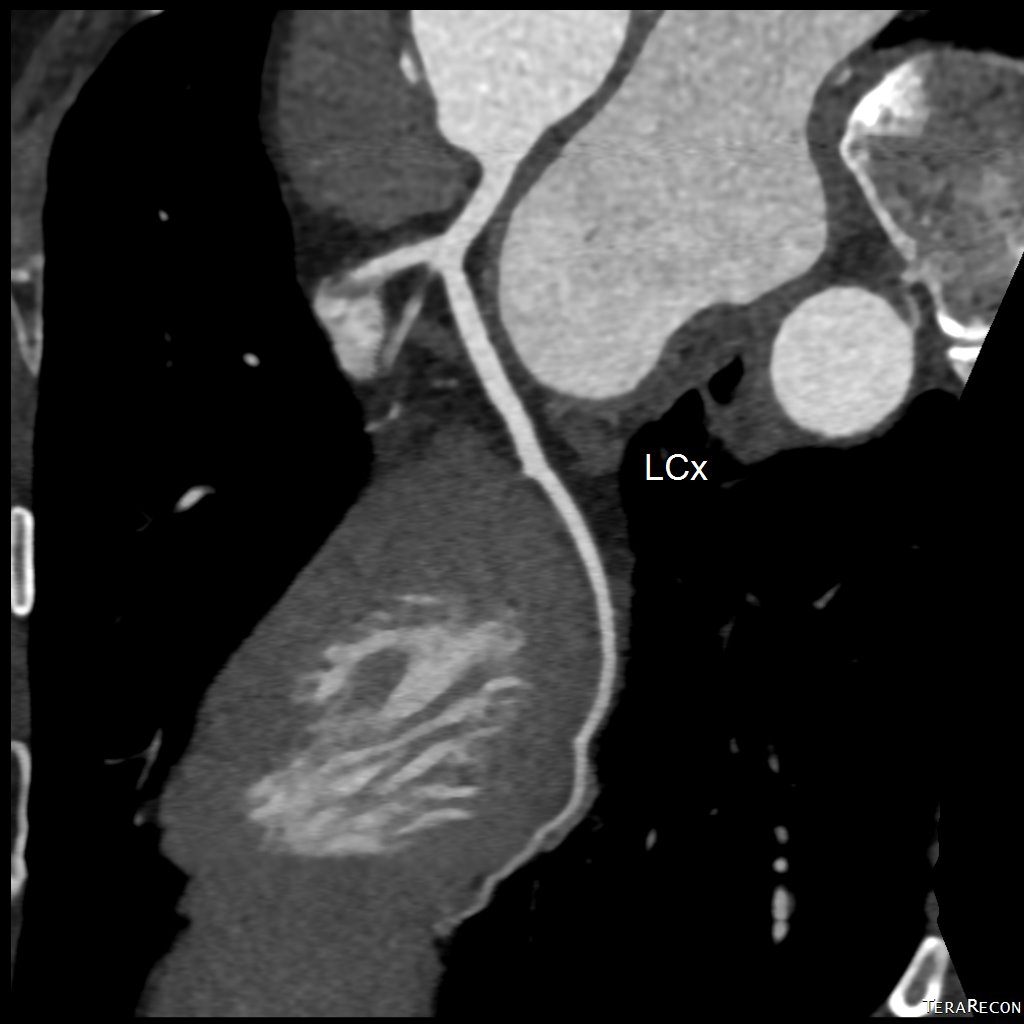

冠狀動脈電腦掃描造影

(CT Coronary Angiogram)

冠狀動脈CT造影 是目前評估心血管疾病風險的重要非入侵性工具,可:

• 清楚顯示冠狀動脈有否出現狹窄、阻塞或鈣化

• 為懷疑有心絞痛或心肌缺血的患者提供早期診斷依據

• 協助心臟科醫生決定是否需進一步介入性治療,如通波仔(PCI)